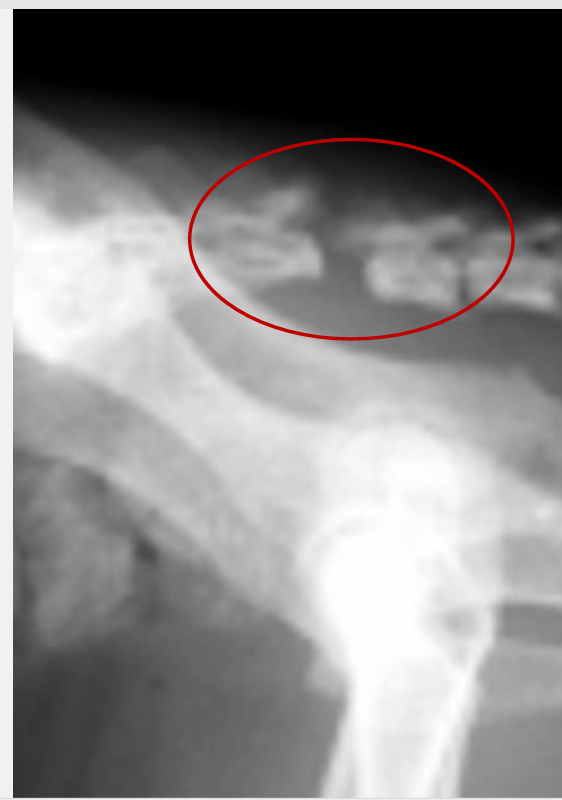

Instabilité atlanto-axiale: diagnostic

Radiographies de la colonne :

vue latérale +/- VD

Px bon si ttt chir